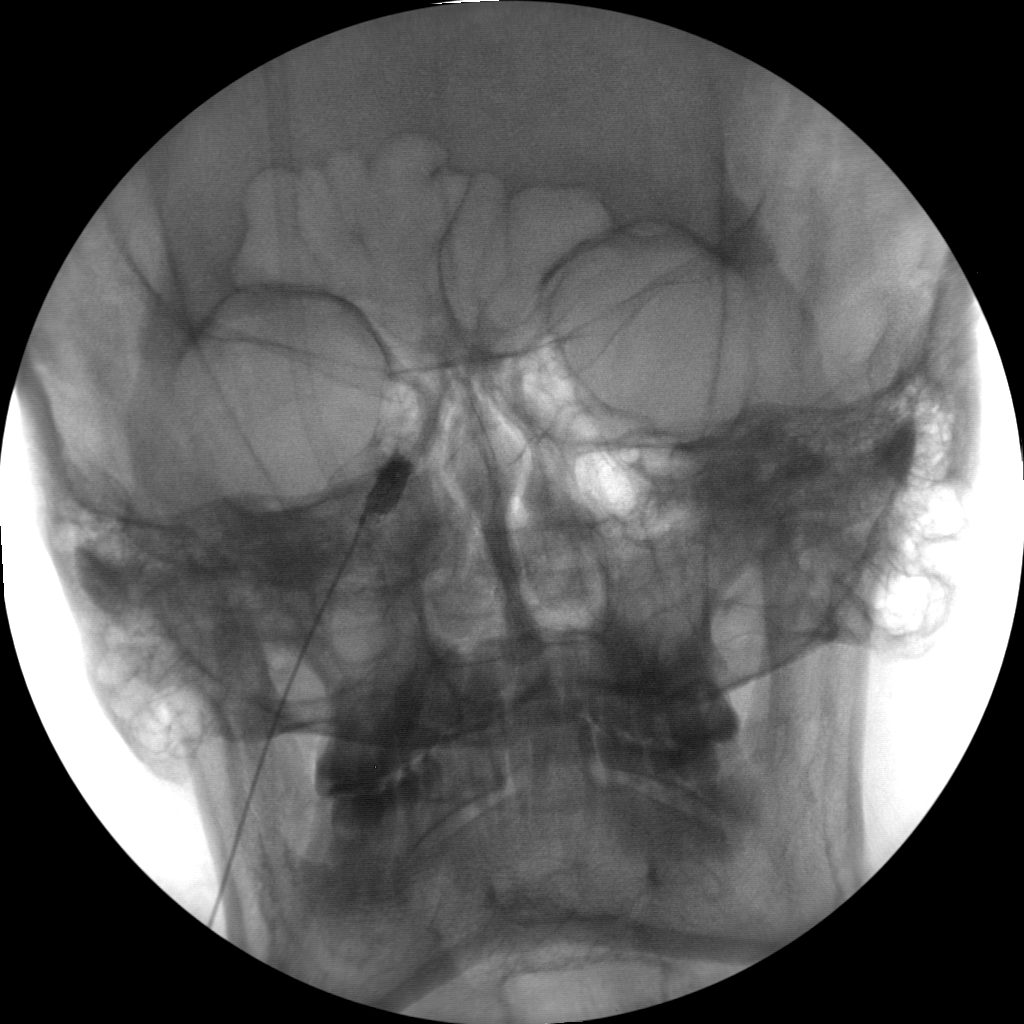

The high-resolution 1kx1k images from Skan-C helps pain management professionals visualize the position of the needle in relation to the epidural space, ensuring accurate and effective treatment.

Skan-C uses advanced imaging technology, such as pulsed fluoroscopy and digital subtraction angiography, to provide highly detailed images of the affected area. This allows doctors to perform procedures with increased precision and accuracy, and better patient outcome